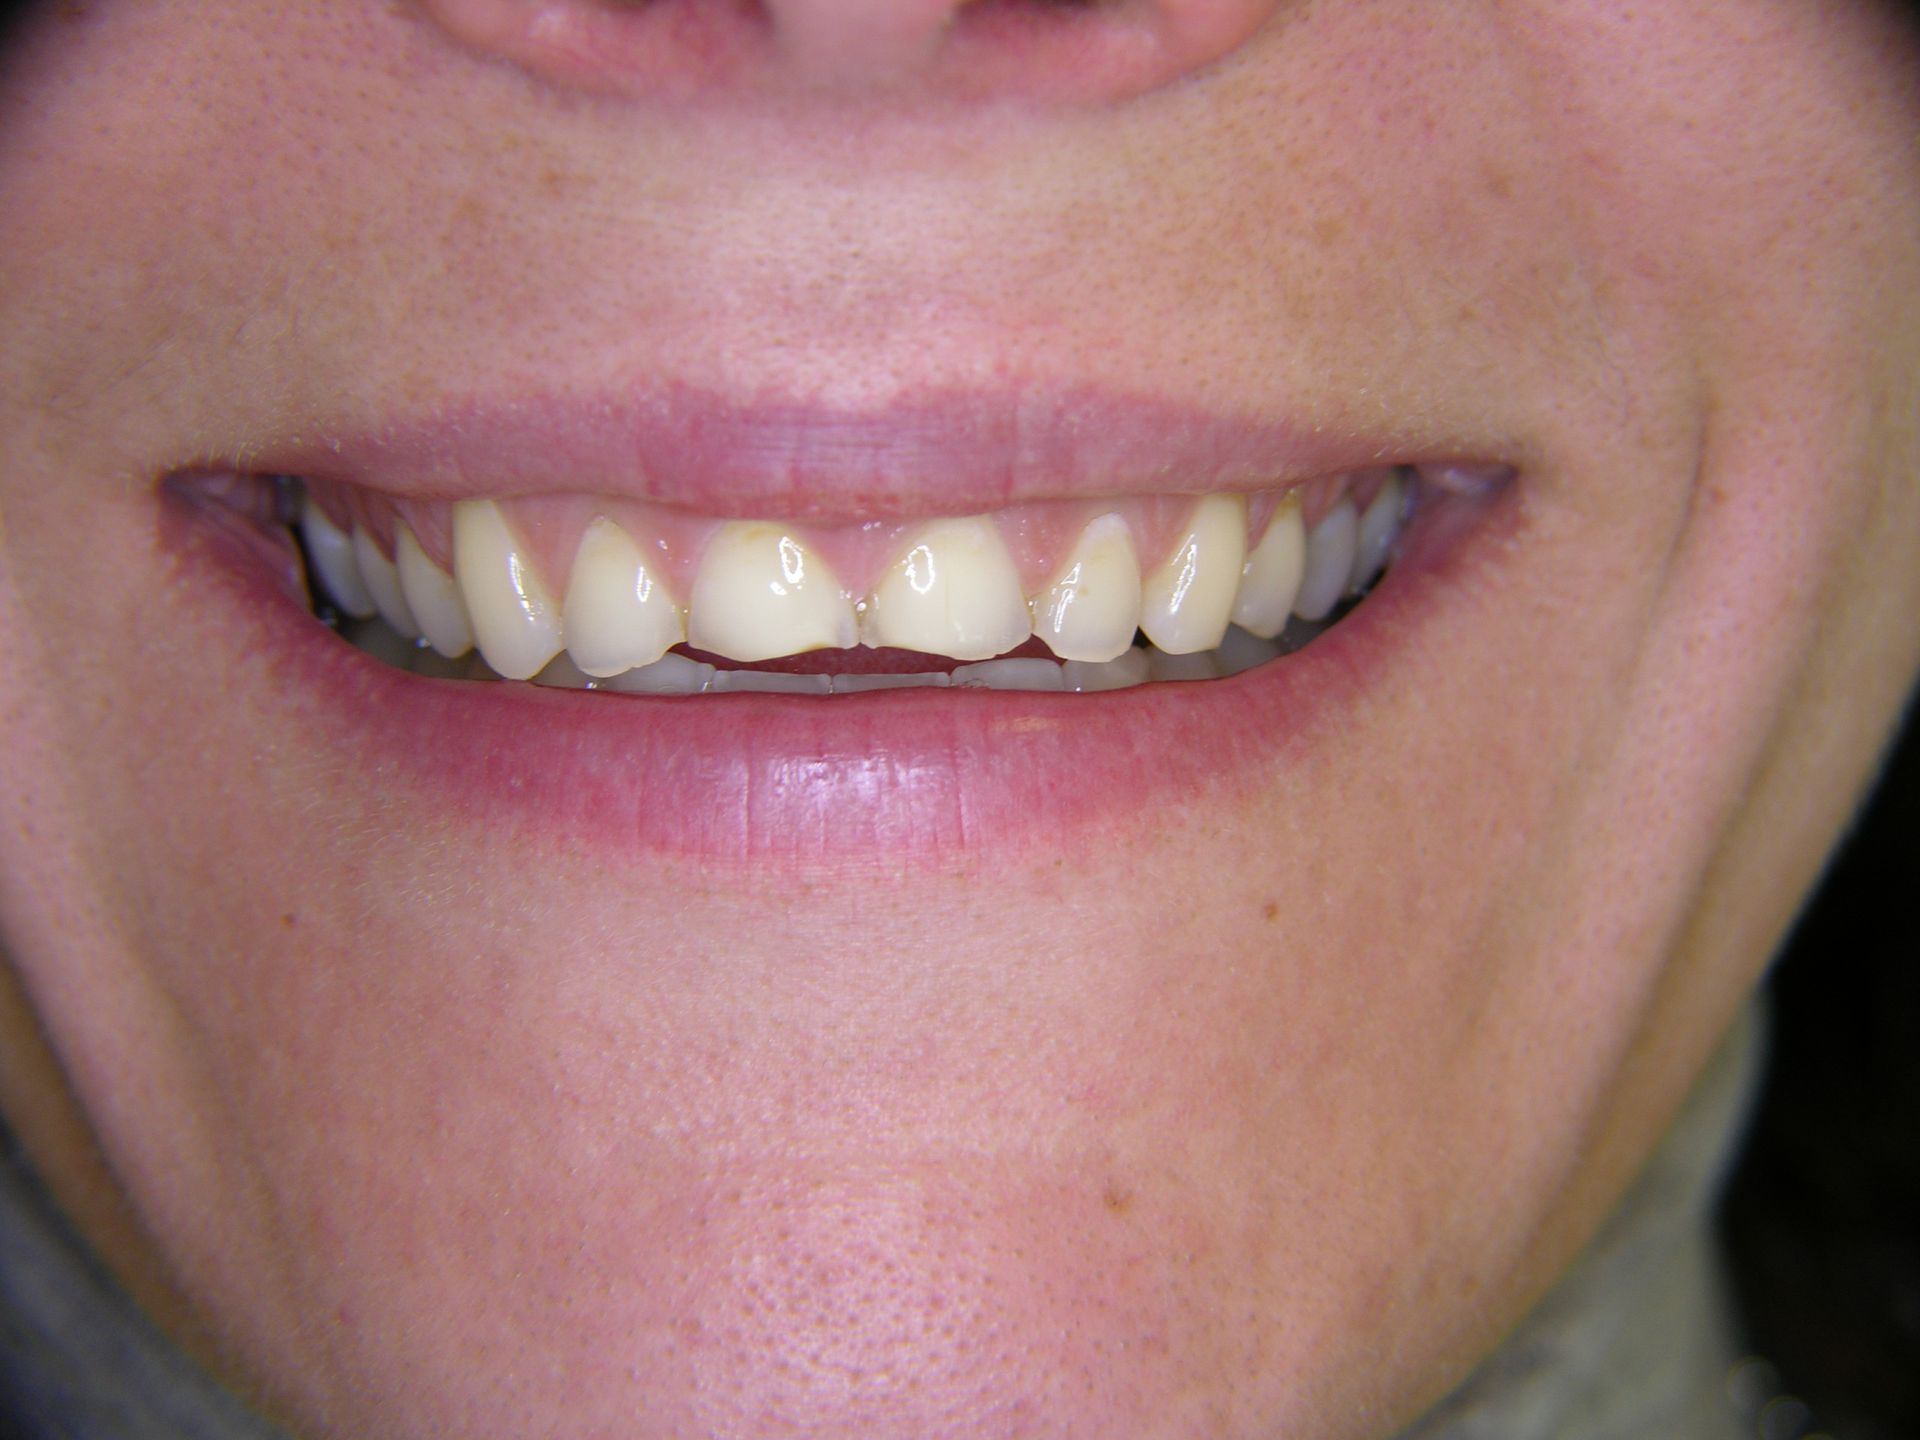

Beispiele von Versorgungen